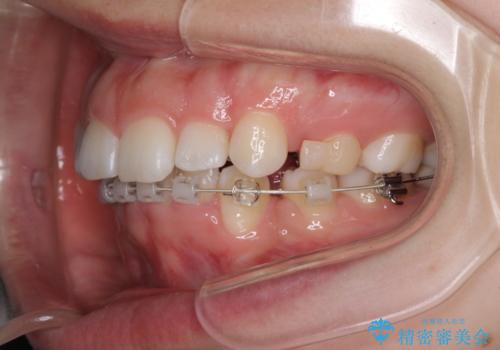

- ハーフリンガル

目立たない装置を希望されたので、上顎が裏側装置のハーフリンガルを選択し、上下左右の小臼歯(計4歯)を抜歯して矯正治療を行うこととしました。

治療期間の目安は2年半~3年間でしたが、咬み合わせにより上顎装置が頻繁に脱落してしまい、治療期間が長期化してしまいました。